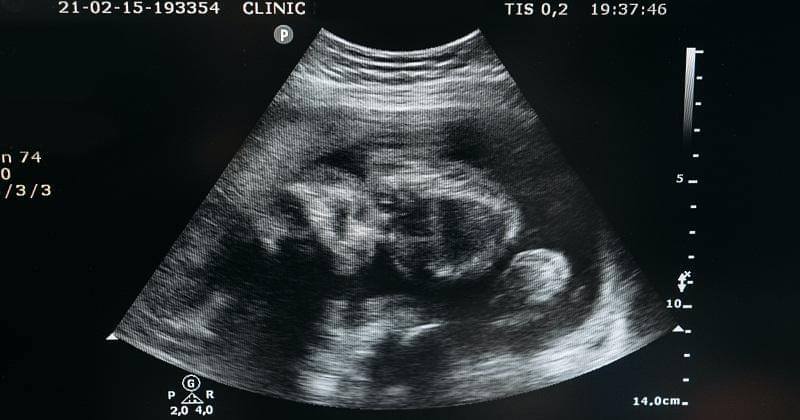

Penyebab lain mengapa janin tidak bergerak adalah mengalami gangguan pertumbuhan. Gangguan pertumbuhan ini juga dapat diketahui saat Mama melakukan pemeriksaan kehamilan.

Misalnya bila janin lebih kecil jika dibandingkan dengan janin normal pada usia kehamilan yang sama, maka biasanya gerakannya tidak terlalu terasa.